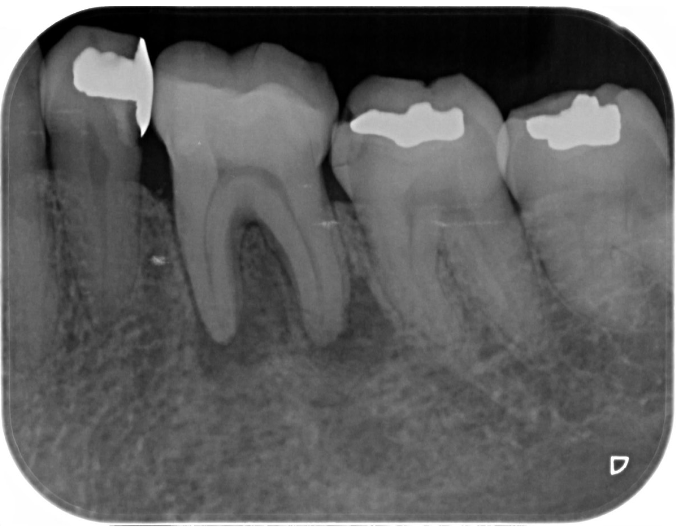

症例2

| 項目 | 詳細 |

|---|---|

| 患者様データ | 60代 男性 |

| 来院時の主訴 | 「歯石が溜まりやすい。歯磨きすると出血するのも治したい。」 |

| 医院の診断 | 歯周病 |

| 通院期間 |

3か月 |

| 来院回数 | 6回 |

| 治療費 | 総額:保険適用診療 【内訳】 歯周病検査・歯磨きや生活習慣指導・歯石取りクリーニング |

| リスクと副作用 | メインテナンスが必要、正しい歯磨き習慣が必要不可欠 |

| ここがこだわりのポイント!☝ | 歯周病の原因は様々ですが、メインの原因は細菌感染です。こちらは中等度の歯周病で来院された患者様です。日々の歯磨き習慣を見直していただき、正しいブラッシング法を身につけたことで健康な歯肉を取り戻しました!こちらの治療結果も患者様の努力の賜物です! |